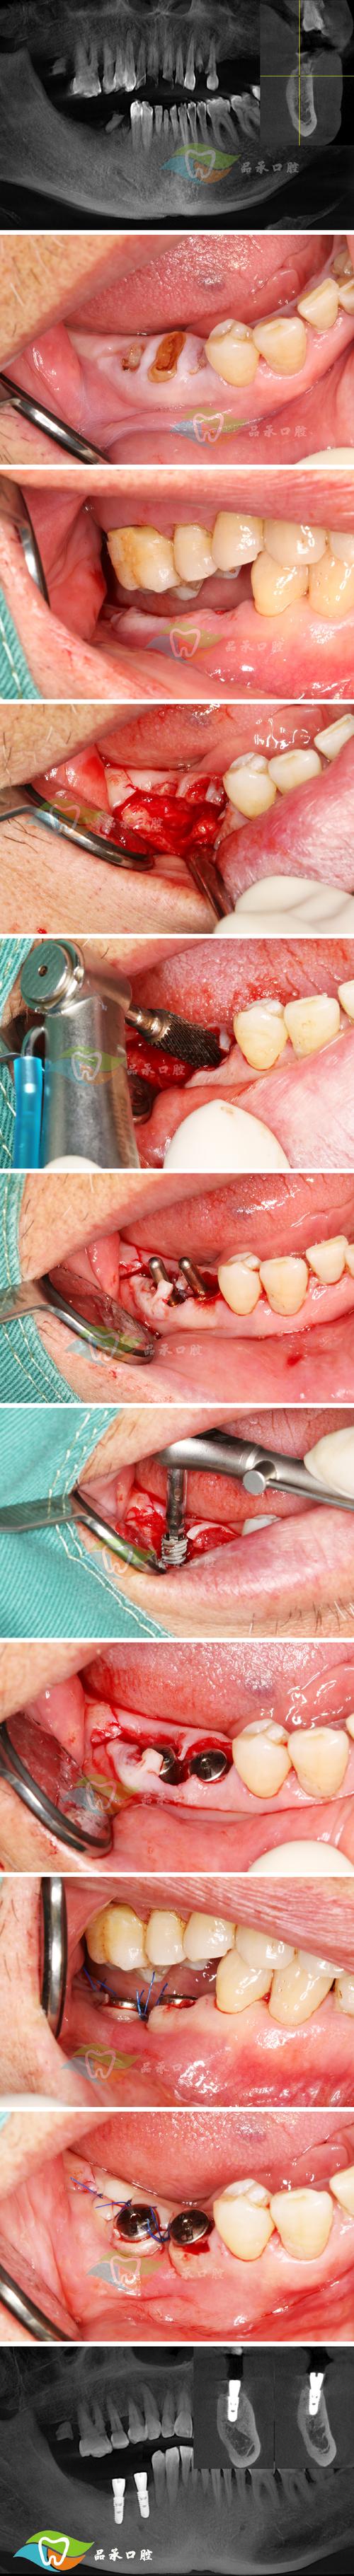

种牙(种植牙)手术后,缝线(缝合线)所在的部位是手术切口的位置,是整个种植体植入的关键区域,术后对这个部位的护理至关重要,直接关系到手术的成功和愈合速度,以下是关于种牙后缝线部位的重要信息和护理要点:

- 作用: 缝线的主要目的是将手术切口处的牙龈组织精确地缝合在一起,覆盖住种植体(骨结合部分),促进伤口愈合,减少感染风险,并形成良好的“袖口”(牙龈袖口),为未来牙冠提供健康的软组织基础。

(图片来源网络,侵删)